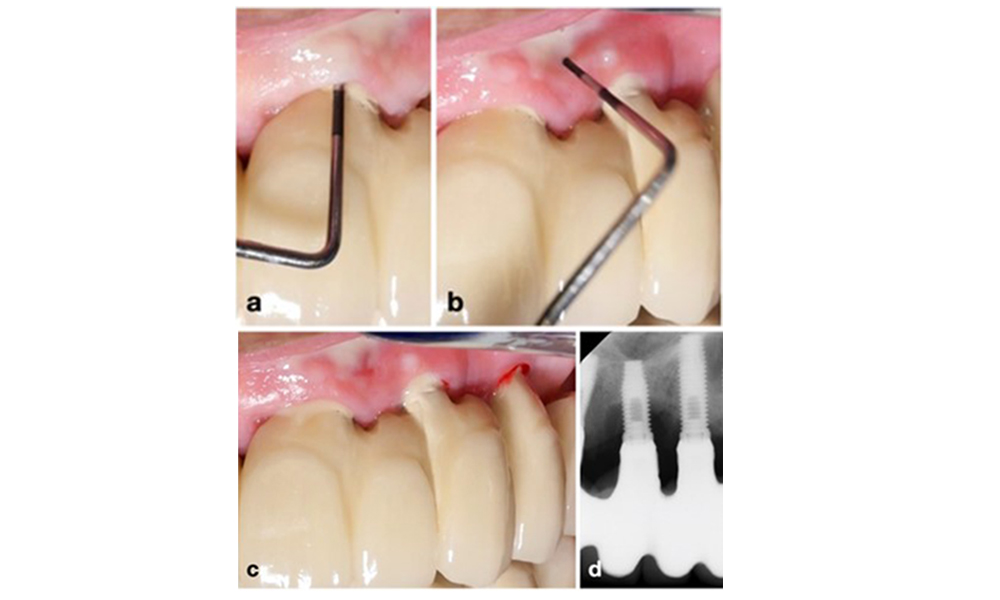

Периимплантитът се идентифицира чрез (1) признаци на възпаление, подобни на мукозит, (2) рентгенографски данни за загуба на кост след първоначалното заздравяване и (3) увеличаване на дълбочината на сондиране в сравнение с измерванията, направени малко след поставянето на протезната реконструкция (фигура 2) . При липса на предишни рентгенографии, рентгенографско костно ниво ≥ 3 mm и кървене при сондиране и дълбочина на сондиране ≥ 6 mm показват периимплантит.

Възстановяване на цяла зъбна дъга с различна степен на периимплантит при някои от имплантите. Имплантът в позиция 21 е силно засегнат с дълбочина на сондиране до 9 mm (a), кървене при сондиране и образуване на гной в периимплантния сулкус и вестибуларна фистула (b–c); рентгеновата снимка показва приблизително 50% костна загуба за импланта с периимплантит в позиция 21, докато имплантът в позиция 23 показва само ограничена костна загуба, съответстваща приблизително на това, което може да се очаква след първоначалното заздравяване за този тип импланти (d).

Фигура 2. Възстановяване на цяла зъбна дъга с различна степен на периимплантит при някои от имплантите. Имплантът в позиция 21 е силно засегнат с дълбочина на сондиране до 9 mm (a), кървене при сондиране и образуване на гной в периимплантния сулкус и вестибуларна фистула (b–c); рентгеновата снимка показва приблизително 50% костна загуба за импланта с периимплантит в позиция 21, докато имплантът в позиция 23 показва само ограничена костна загуба, съответстваща приблизително на това, което може да се очаква след първоначалното заздравяване за този тип импланти (d).

Очакваната костна загуба след първоначалното заздравяване се дължи на маргиналното костно ремоделиране и варира в зависимост от фактори като имплантна система или типа имплант. Например загуба на 1–2 mm кост обикновено се счита за „нормална“ за импланти на нивото на костта с външна връзка (фигура 2d, имплант в позиция 23).